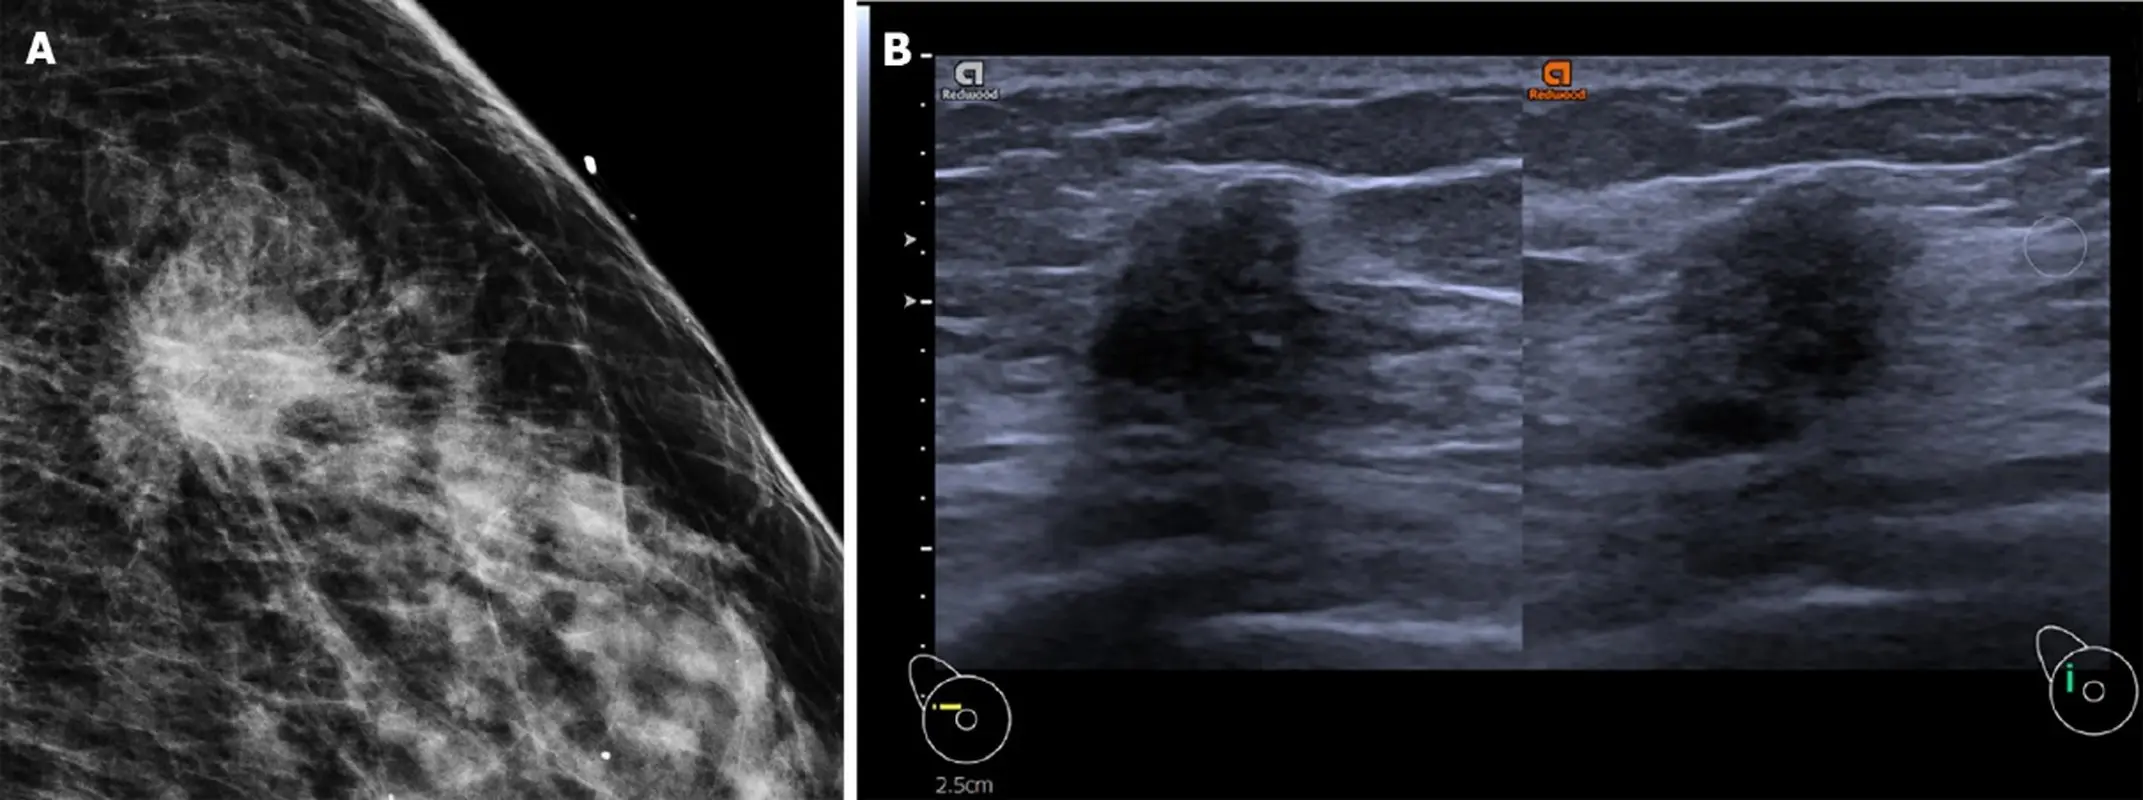

سونوگرافی سینه با استفاده از امواج صوتی با فرکانس بالا، تصویری از بافت داخلی پستان ایجاد میکند. این امواج پس از برخورد با بافتها بازتاب پیدا میکنند و دستگاه، بر اساس این بازتابها تصویر تولید میکند. در بررسی تودههای مشکوک، سونوگرافی میتواند توده جامد را از کیست پر از مایع تفکیک کند، شکل و حاشیه توده را نشان دهد، میزان خونرسانی به توده عمق و محل دقیق ضایعه را ارزیابی کند.

تودههای سرطانی معمولاً ویژگیهایی مانند حاشیه نامنظم، شکل غیرمتقارن و نفوذ به بافت اطراف دارند. اما برخی ضایعات خوشخیم نیز میتوانند ظاهری مشابه ایجاد کنند. به همین دلیل نتیجه سونوگرافی باید توسط رادیولوژیست تفسیر شود. در شرایطی که فرد امکان مراجعه حضوری ندارد یا نیاز به خدمات تشخیصی سریع دارد، برخی مراکز معتبر خدمات انجام سونوگرافی در منزل ارائه میدهند که میتواند برای سالمندان، مادران باردار یا بیماران با محدودیت حرکتی گزینه مناسبی باشد.